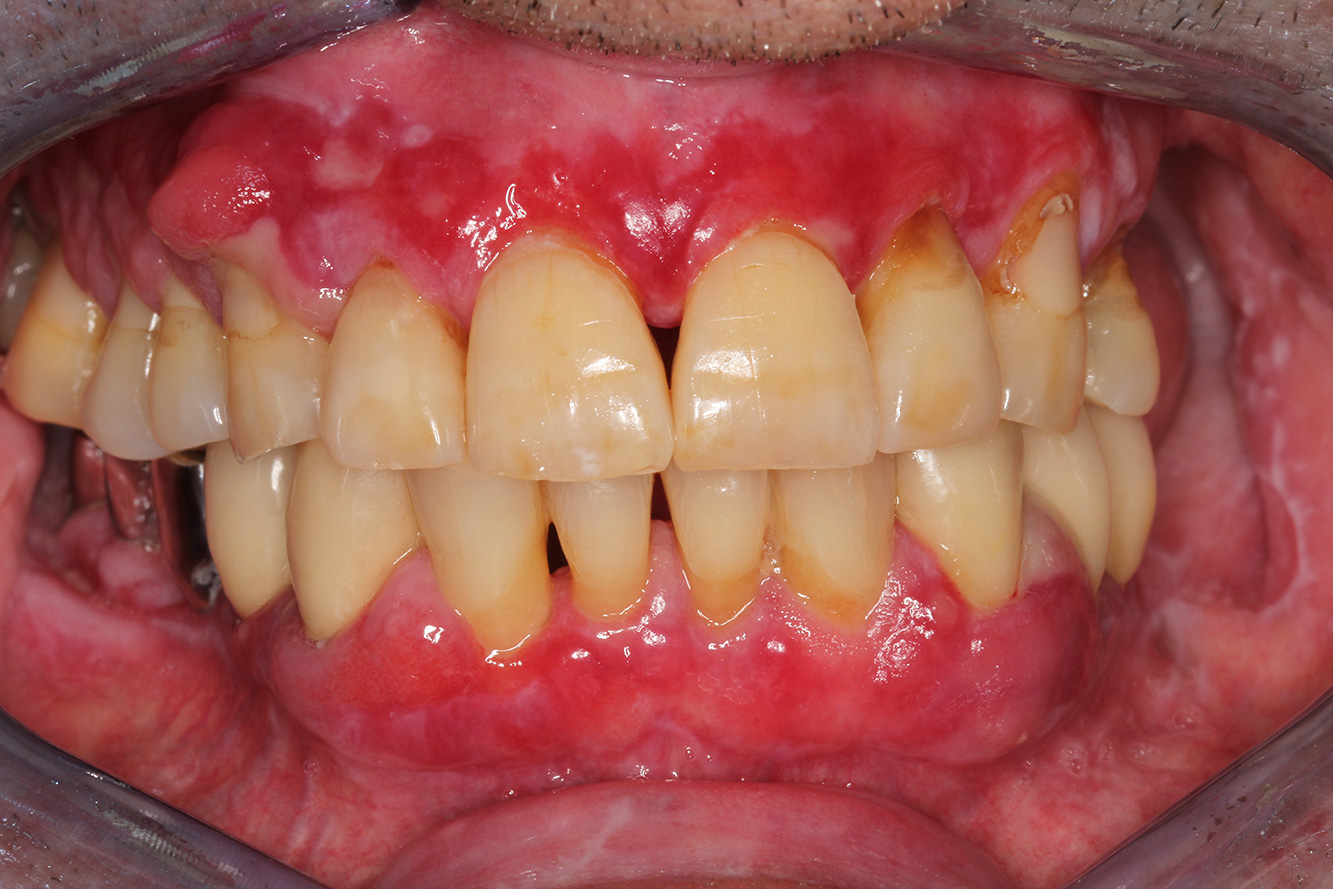

The healthy patient with pre-existing periodontal disease & peri-implantitis

The 28-Year-Old Cigarette Smoker with Dental Erosions